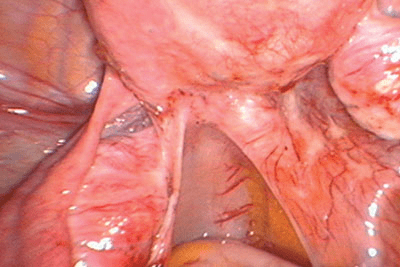

Figure 8 : Ces glandes individualisées d’une endométriose superficielle du ligament large gauche n’ont pas été détruites par la vaporisation laser, alors que des adhérences fines et transparentes sont une conséquence du traitement au laser (pour l’aspect microscopique, voir la figure 9).

Figure 9 : Une glande d’endométriose (astérisque) se trouve juste au-dessous du péritoine de la patiente (figure 8). Des adhérences transparentes (flèche) peuvent se développer suite à un dégât de la chirurgie au laser.

Figure 10 : Une endométriose biologiquement active du ligament large gauche est associée à des épaisses lésions cicatricielles jaunâtres et à du sang emprisonné sous la surface du péritoine (en rétropéritonéal). L’uretère se trouve au-dessous de la lésion.

Figure 11 : Une exérèse agressive radicale de la lésion montrée dans la figure 10 requiert une urétérolyse. L’uretère gauche (flèche) était atteint par une légère fibrose rétropéritonéale qui s’était étendue depuis le nodule fibreux péritonéal (à l’intérieur du cercle).

Figure 12 : Le rectum est légèrement arrondi (flèche) à l’endroit où il rejoint le ligament utéro-sacré droit. Cette forme arrondie montre que la paroi rectale est atteinte d’endométriose et nécessitera une forme de chirurgie digestive pour enlever complètement le foyer. Le cul de sac à gauche du rectum montre des lésions glandulaires superficielles d’endométriose entourées de cicatrices stellaires.

Figure 13 : La paroi postérieure de l’utérus montre plusieurs taches hémorragiques représentant soit une adénomyose, soit une endométriose avec une néovascularisation contiguë. L’exérèse de l’endométriose ne soignera pas les symptômes utérins révélés par ces découvertes et qui ne sont pas dus à l’endométriose. Le cul de sac est complètement obstrué, mais la paroi rectale est lisse, ce qui indique qu’il y a très peu où pas d’endométriose rectale. L’ovaire gauche est kystique et caché sous des sinuosités péritonéales accolées au ligament utéro-sacré gauche. Des lésions glandulaires superficielles d’endométriose touchées par une fibrose légère peuvent être observées sur le ligament large droit.